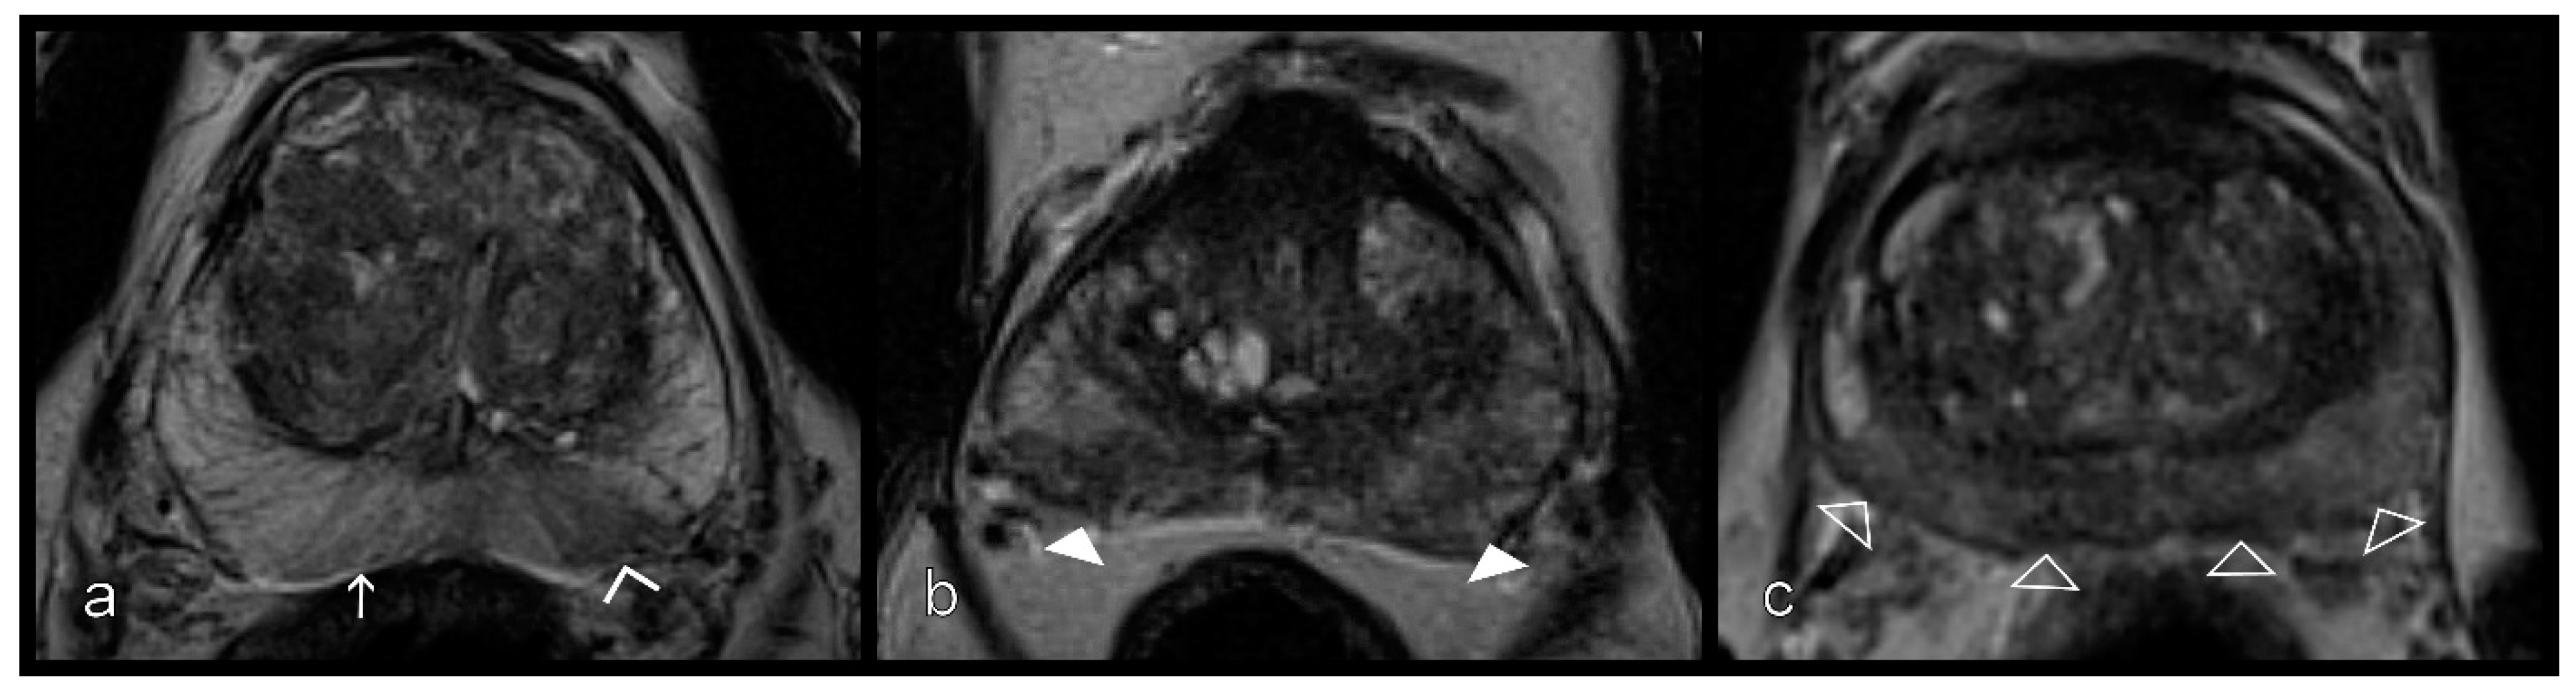

Figure 2.

Reference standard. Imaging findings showing patchy T2W signal attenuation (white arrows) in the peripheral zone on both sides (a), moderate reduction (white arrowheads) in the ADC map (b), and diffuse enhancement (empty arrowheads) in the dynamic T1W VIBE (c); Formally, this represents the PI-RADS 3 constellation; (d) The MRI/ultrasound (US)-guided biopsy 3D model depicts the target lesions in the blue zones and the template biopsy cores (numbered). Pathology confirmed no malignancy. ADC, apparent diffusion coefficient; T1W, T1-weighted; T2W, T2-weighted; VIBE, Volumetric interpolated breath-hold examination.